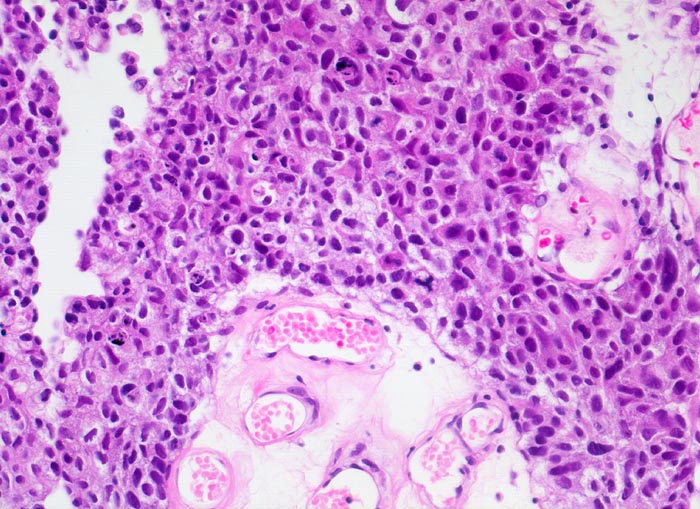

PathoPic – image database / PathoPic ID 3996 - Wenig differenziertes papilläres Urothelkarzinom G3

Wenig differenziertes papilläres Urothelkarzinom G3

maligner Tumor

Harnblase

Niere, Harnwege

Stromainvasion an anderer Stelle und assoziiertes Carcinoma in situ.

Papillärer Harnblasentumor. Makrohämaturie.

Histologie

200